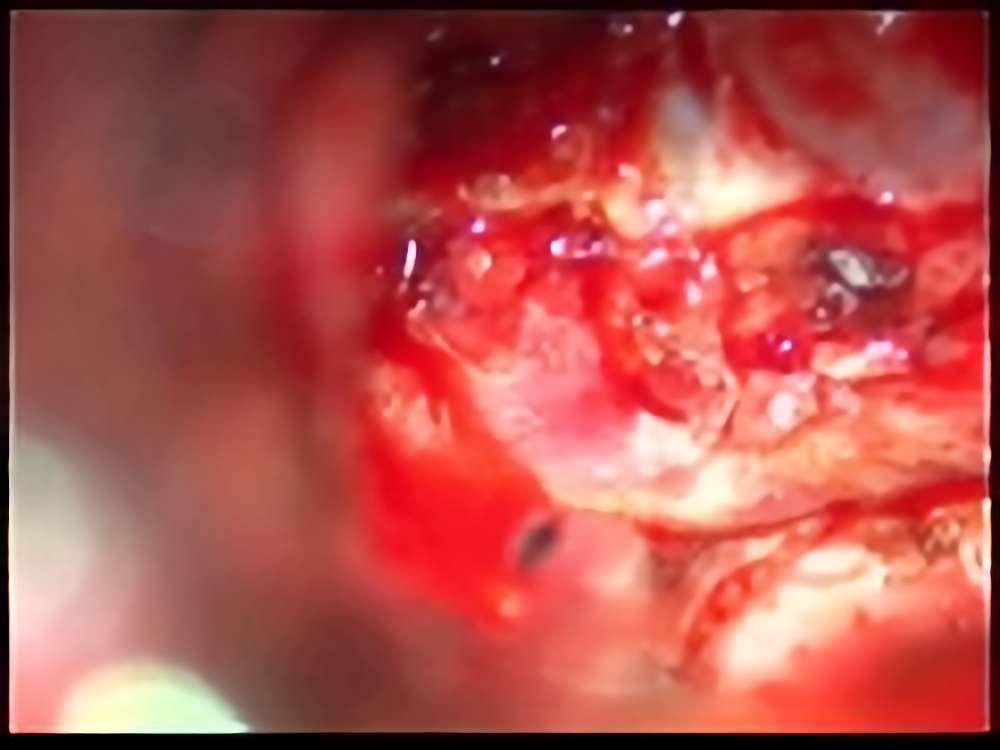

No.’15_13 摘出 前

No.’15_13 摘出 後